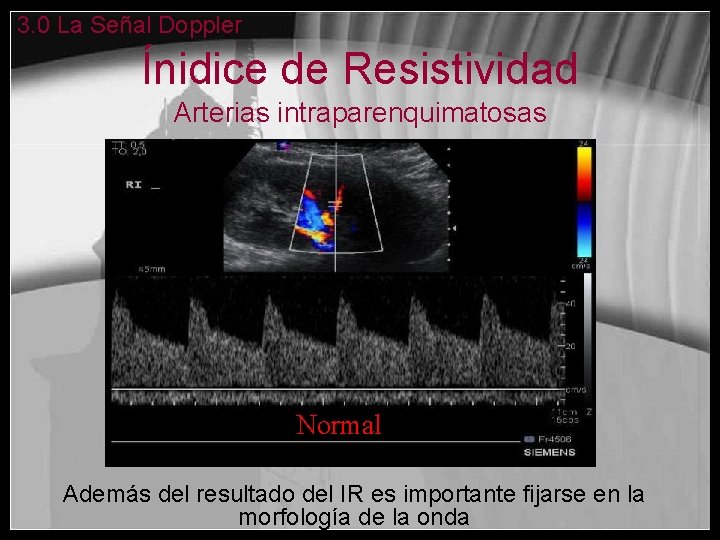

Ínidice de Resistividad Arterias intraparenquimatosas • Es la relación entre la sístole y la diástole (velocidad pico sistólica– veloc. final diastólica/ veloc. pico sistólica) • El ángulo no tiene que ser corregido porque es un cociente • Riñónes – IR Normal : 0, 6 -0, 8 • IR elevado: se observa en edema, vasoconstricción, trombosis venosa… • IR bajo: se observa distalmente a una estenosis (flujo tardus-pardus)

3. 0 La Señal Doppler Ínidice de Resistividad Arterias intraparenquimatosas Normal Además del resultado del IR es importante fijarse en la morfología de la onda